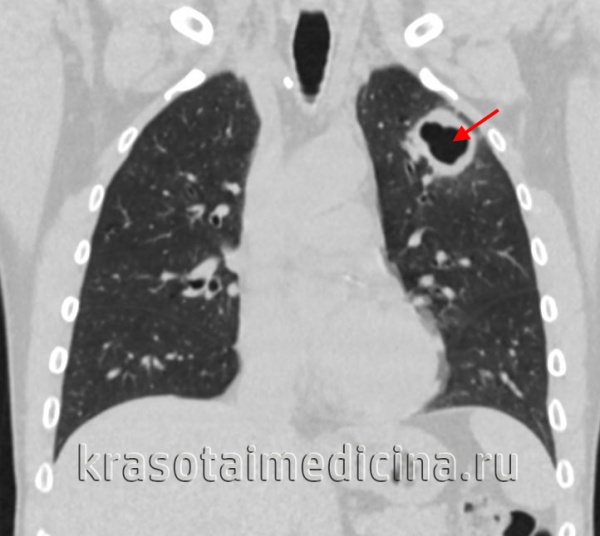

Туберкулома — это, как правило, округлый, покрытый фиброзной капсулой фокус казеозного некроза диаметром не менее 1,5—2 см. Фиброзная капсула туберкуломы практически непроницаема для циркулирующих и крови туберкулостатичсских препаратов. В тубсркуломе среди казеозных масс могут быть остатки элементов легочной паренхимы, эластических волокон, стенок сосудов или бронхов. Иногда в туберкуломах наблюдаются известковые включения. У многих больных с туберкуломамн легких имеются различные признаки активности туберкулезного процесса и отмечается его прогрессировать. Более часто прогрессировать наблюдается в тех случаях, когда в туберкуломе имеется pacпад, а также при наличии в одной доле легкого нескольких туберкулом.

Операция по поводу туберкуломы показана во всех случаях, когда течение туберкулезного процесса осложняется периодическими обострениями, которые проявляются субфебрнльной температурой и симптомами интоксикации, при бацилловыделении, увеличении размеров туберкуломы или появлении в ней полости распада, множественных туберкуломах в одной доле легкого, туберкуломах диаметром более 2—3 см, специфическом поражении бронхов. Прямым показанием к операции является также трудность дифференциальной диагностики между туберкуломой и периферическим раком легкого. В некоторых случаях показанием к оперативному лечению может быть препятствие к работе по специальности (педагоги, врачи-педиатры, работники пищеблоков и др.).

Туберкулома легкого

Представляет собой инкапсулированный казеозный очаг, сформировавшийся в исходе инфильтративного, очагового или диссеминированного процесса. При стабильном течении симптомы не возникают, образование выявляется при рентгенографии легких случайно. В случае прогрессирующей туберкуломы легкого нарастает интоксикация, появляется субфебрилитет, боль в груди, кашель с отделением мокроты, возможно кровохарканье. При распаде очага туберкулома может трансформироваться в кавернозный или фиброзно-кавернозный туберкулез легких. Реже отмечается регрессирующее течение туберкуломы.